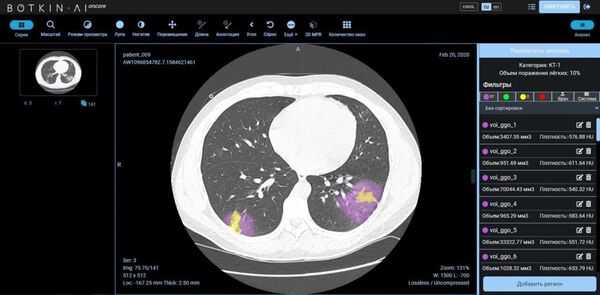

Trả lời phỏn vấn của Sputnik, ông Alexey Fomin, Giám đốc phát triển kinh doanh của công ty Intellogic (Botkin.AI) cho biết bằng cách nào công nghệ AI giúp xác định tình trạng tổn thương phổi, nói về những sai sót có thể xảy ra, về tính khả dụng của phương pháp này và các tiêu chí lựa chọn bệnh nhân để nghiên cứu.

A. Fomin: Kết quả nghiên cứu được phân tích bằng cách ứng dụng trí tuệ nhân tạo (AI) - mạng lưới thần kinh nhân tạo - theo mấy giai đoạn. Đầu tiên, hệ thống này lựa chọn các khu vực bệnh lý (phân chia chuẩn mực / bệnh lý), sau đó các khu vực được chọn đi qua một chuỗi các mạng lưới thần kinh để phát hiện những dấu hiệu cho bệnh lý cụ thể trong từng khu vực. Sau khi tất cả các khu vực được đánh dấu, AI đếm các thể tích và đưa ra đánh giá tổng thể về các khu vực bị tổn thương.

A. Fomin: Tổng thời gian phụ thuộc vào những đặc điểm của tích hợp được thực hiện, cũng như chất lượng của nghiên cứu. Nếu chúng tôi ước tính thời gian phân tích bằng mạng nơron Botkin.AI thì quá trình này chỉ mất từ 2 đến 5 phút.

A. Fomin: Nền tảng Botkin.AI đã sẵn sàng để được sử dụng đại trà và hỗ trợ cho các bác sĩ X quang. Ngày nay nền tảng Botkin.AI là nền tảng đầu tiên và duy nhất được Roszdravnadzor phê duyệt như một thiết bị y tế loại 2b. Công ty Intellogic sẵn sàng hợp tác với đại diện của các cơ quan y tế khu vực để phân tích kết quả nghiên cứu cũng như với các cơ sở y tế tư nhân.